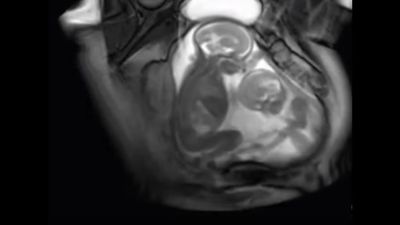

Në videon e mëposhtme, mund të shihen dy fëmijë në mitrën e nënës duke lëvizur në hapësirat e tyre dhe duket se po bëjnë mundje me njëri-tjetrin dhe pastaj po kërkojnë falje.

Foshnja në të djathtë shihet si më dominues, ndërsa ai në të majtë më i kujdesshëm. Njëri shihet tek e godet tjetrin, përderisa tjetri e puthë atë në ballë.